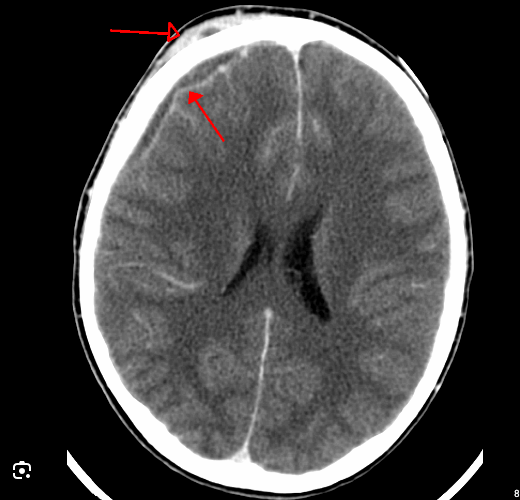

21

Q

o que verifica nessa imagem

A

empiema subdural

• inflamação do espaço subaracnóideo pode difundir transudato através da aracnoide, que se acumula no espaço subdural, formando a coleção subdural

• Quando a coleção subdural se infecta ou quando o espaço é alcançado por exsudato purulento, forma-se o empiema subdural.

• frequente em recém-nascidos até 1 ano de vida